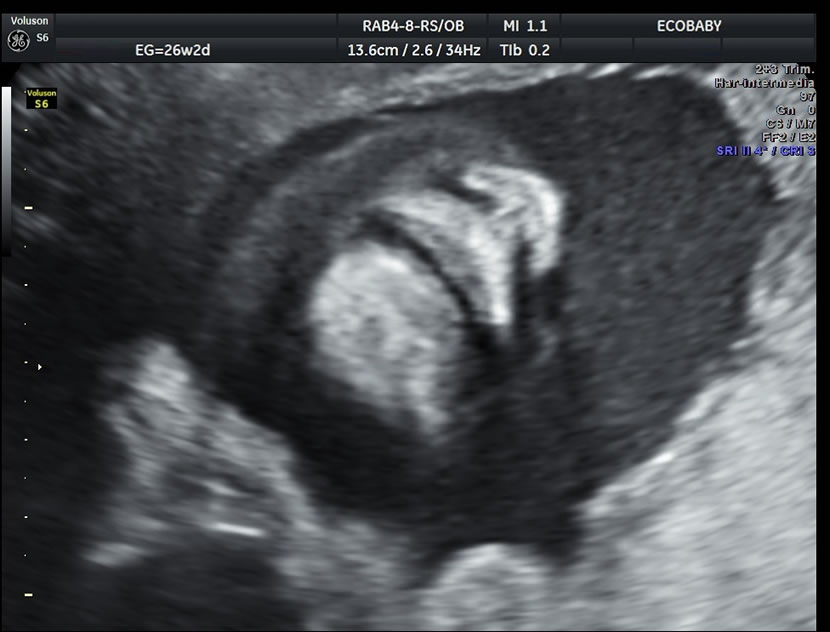

Cerebro, cuello, cara, tórax, corazón (diferentes cortes que muestran las cavidades y la correcta entrada y salida de arterias y venas), abdomen (normalidad de la pared, estómago, intestino, riñones, vejiga), miembros inferiores y superiores y columna vertebral.